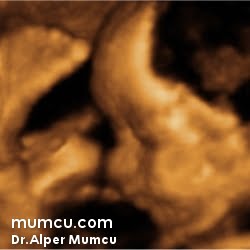

3 Boyutlu ultrason resimleri

Bu sayfadaki fotoğraflar degişik zamanlarda ve farklı hastalarda Dr. Alper Mumcu tarafından çekilmiştir.

8 haftalık gebelik